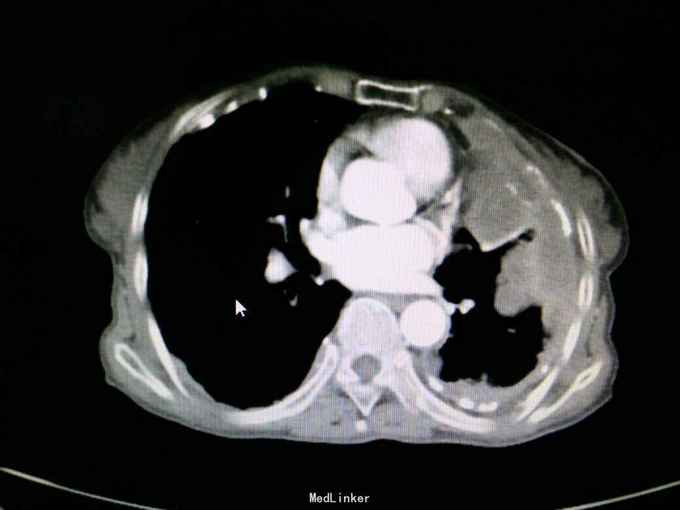

查体:神志清,精神可,生命体征平稳。两肺呼吸音粗,未闻及干湿性啰音。 辅查: 血气分析:PH7.43, 二氧化碳分压43mmHg, 氧分压77mmHg, 氧饱和度95%。 血常规:WBC7.5x10∧9/L, NE77.8%, Hb132g/L, plt231x10∧9/L。 尿常规,粪便常规,凝血功能,肿瘤标志物,CRP, 免疫功能,肝肾功能电解质无明显异常。 痰培养,痰找抗酸杆菌阴性。 心电图无明显异常。 心脏彩超:主动脉瓣局部退行性变,左室舒张功能减退,轻度肺高压。 腹部B超无异常。 胸部增强CT:双侧多发胸膜斑,左侧胸膜弥漫结节状及团块形成,考虑石棉肺伴左侧胸膜继发性恶性间皮瘤可能。

入院诊断:左侧胸膜肿物:胸膜间皮瘤? 诊治经过:予对症支持治疗,行CT引导下胸膜活检 病理:结合免疫组化和临床病史,符合恶性间皮瘤。 治疗:患者明确诊断后予化疗前预处理,择期行培美曲塞+铂类化疗